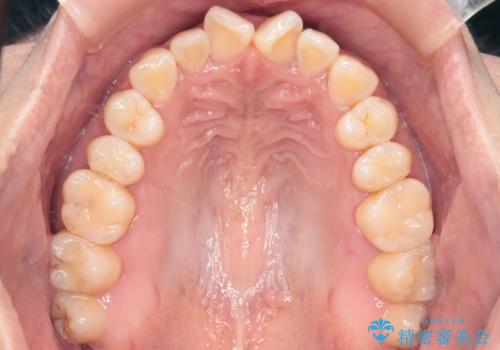

【インビザライン】前歯の捻れ気になる

- 上の前歯の捻れを主訴に来院されました。

前歯の捻れとがたつきを改善するために、IPR(歯と歯の間を削る処置)と歯列拡大をすることで歯並びを整えていく治療計画を立てました。

かみ合わせを整えるためにゴム掛けも行いながら、治療していきました。

患者様にマウスピースの使用とゴム掛けを頑張っていただいたおかげでリファイメント(マウスピースの再発注)も1回で終了することができました。